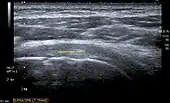

Transversal ultra sonography of the supraspinatus tendon